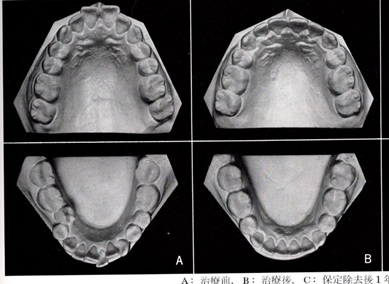

Aは抜歯矯正治療前、Bは抜歯矯正治療後です。

AからBの移行時に第1小臼歯を上下4本抜いています。

そのために、上下顎の歯列弓が短縮されています。

特に下顎は舌の収納場所であるため、下顎の歯列弓が縮小すると舌が奥に引き込まれて下の右の図にあるように、無呼吸を起こしやすくなる形態を作ってしまいます。

A:治療前 B:治療後